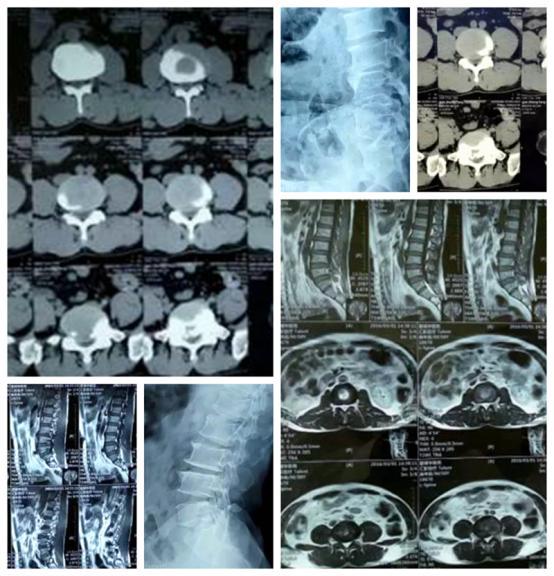

經(jīng)專家組討論,認為王診斷明確,建議盡快按照計劃手術(shù),避免神經(jīng)壓PO再加重。手術(shù)可以采用椎間孔鏡手術(shù)。 在椎間孔鏡下切除患者突出髓核,手術(shù)很成功。術(shù)后,患者癥狀很快消失。 患者:王**,女,48歲。 住院號:27**91 住院日期:2016/06/21。 主訴:腰痛1年,加重伴左下肢麻木2月。 現(xiàn)病史:1年前勞累后出現(xiàn)腰部疼痛,并活動受限,無下肢放射痛及麻木,在當(dāng)?shù)蒯t(yī)院給予藥物(具體不詳)、理療、休息后疼痛緩解。2月前勞累及受涼后腰痛加重伴有左下肢放射性疼痛及麻木,疼痛呈刀割樣,坐起及活動后疼痛加重,休息后稍緩解,無間歇性跛行,僅能在床邊活動,嚴(yán)重影響日常生活,行CT檢查提示:L4-5椎間盤突出,為求進一步診治住院。發(fā)病以來神志清,精神差,無發(fā)熱咳嗽,無低熱盜汗,局部無皮疹,無夜間痛,無便秘,飲食睡眠欠佳,體重未見明顯變。 主要查體:神志清、痛苦面容,腰椎生理曲度變淺,皮膚顏色正常,無皮疹及色素沉著,L4-5椎旁左側(cè)壓痛(++),并有左下肢放射痛,局部肌肉質(zhì)硬。活動度:前屈(60°)、后伸(15°)、左右側(cè)屈(25°)。左小腿外側(cè)皮膚感覺減退,左直腿抬高試驗陽性(30°),加強試驗陽性,右直腿抬高試驗陰性。仰臥挺腹試驗陽性,股神經(jīng)牽拉試驗陰性。下肢肌肉未見萎縮,左側(cè)踇背伸肌力Ⅳ級,右側(cè)正常。巴彬斯基征(-),VAS:8分。 輔助檢查:CT:L4-5椎間盤突出。MRI:L4-5椎間盤突出。肌電圖:L5神經(jīng)源性損害。 入院診斷: 腰椎間盤突出癥 治療方法: 椎間孔鏡手術(shù)治療。 治療結(jié)果: 1、術(shù)后當(dāng)天,疼痛基本消失。 2、術(shù)后7天,疼痛完全消失。 3、6月后隨訪,患者恢復(fù)良好,疼痛完全消失,未再復(fù)發(fā)。 今年42歲,家住桂林全州的黃先生(化名),兩個月前突然出現(xiàn)腰腿疼痛,久坐久站后疼痛加劇,平躺休息后稍微有所緩解,并伴有左下肢放射性疼痛。起初,他以為是腰肌勞損所致,就去當(dāng)?shù)蒯t(yī)院輸了幾天點滴,但疼痛并未減輕。于是,3月21日進行了詳細的查體并安排相關(guān)檢查,因患者疼痛難忍,隨即安排了住院。第二天,結(jié)合核磁共振檢查發(fā)現(xiàn)黃先生是由于L5/S1椎間盤突出而引起的反復(fù)腰痛伴左下肢放射性疼痛,突出部位在2區(qū),根性癥狀典型,患者為壯年,無明顯椎管狹窄,有微創(chuàng)椎間孔鏡手術(shù)治療的指征。與黃先生溝通后,最終決定采用微創(chuàng)椎間孔鏡術(shù)來摘除椎間盤組織,并制定了周密的手術(shù)計劃。 3月26日,黃先生在局部麻醉下實施了微創(chuàng)椎間孔鏡手術(shù),手術(shù)過程非常順利,歷時不到1小時,手術(shù)傷口只有7毫米,術(shù)中出血僅5ml,術(shù)后立即對黃先生進行直腿抬高試驗測試,當(dāng)黃先生多次抬高肢體時,感覺自己的腰背部及左下肢疼痛消失,手術(shù)圓滿成功。第二天等醫(yī)生查房時,黃先生緊緊握住主任的雙手,高興地說:“手術(shù)結(jié)束后當(dāng)晚,我就可以坐起來,今天就可以自己佩戴腰圍下床自由活動,我終于不用再飽受腰腿痛的煎熬啦!真的很感謝您們,謝謝您們精湛的醫(yī)術(shù)!”看著患者滿懷感激的笑容,在場的醫(yī)務(wù)人員都會心地笑了。再次對他進行了詳細的檢查,并指導(dǎo)術(shù)后康復(fù)治療。 無獨有偶,61歲的蔣大爺和25歲的何姓青年,半個月前也是出現(xiàn)腰痛并下肢放射疼痛,四處求醫(yī),保守治療無效,遂來南溪山醫(yī)院求醫(yī)。經(jīng)過檢查及病例討論,也為他倆進行了椎間孔鏡手術(shù)。術(shù)后不適癥狀即刻緩解,患者們連連為此點贊。